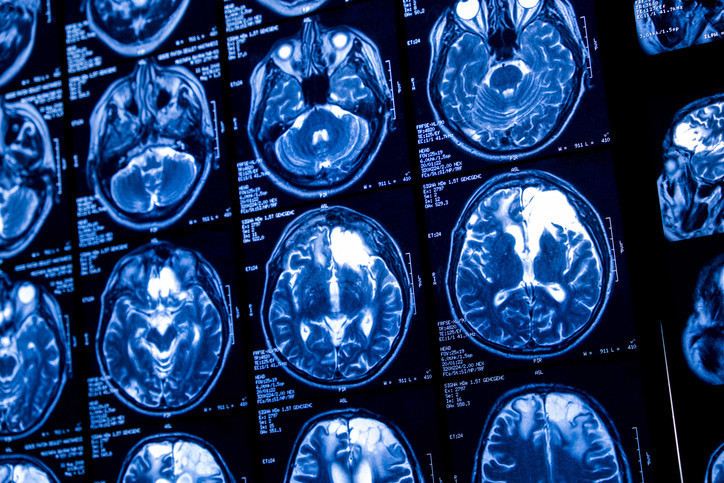

Araştırmada, 22-37 yaşları arasında ana dili Japonca olan dört erkek ve iki kadın gönüllünün beyin aktiviteleri tarandı. Katılımcılar, 2 bin 180 sessiz video klibi izlerken beyinleri fMRI tarayıcılarıyla izlendi. Videolar saniyeler süren sahneler içeriyor ve nesneler, sahneler ile eylemler arasında değişiyordu.

Bu devasa veri seti, büyük dil modelleri ve üretken yapay zeka sistemleri kullanılarak işlendi. Yapay zeka, video kliplerin altyazılarını sayısal dizilere dönüştürdü. Horikawa, beyin aktivitesi ile bu sayısal dizileri eşleştirmek için “kod çözücüler” adı verilen daha küçük yapay zeka modelleri geliştirdi.

Eğitim sürecinden sonra katılımcılar, yapay zekanın daha önce karşılaşmadığı videoları izlerken veya hatırlarken beyin aktiviteleri kod çözücülerle yorumlandı. Ardından, bir algoritma bu kodlanmış beyin aktivitelerine en uygun kelime dizilerini üreterek tanımlayıcı metinler oluşturdu.